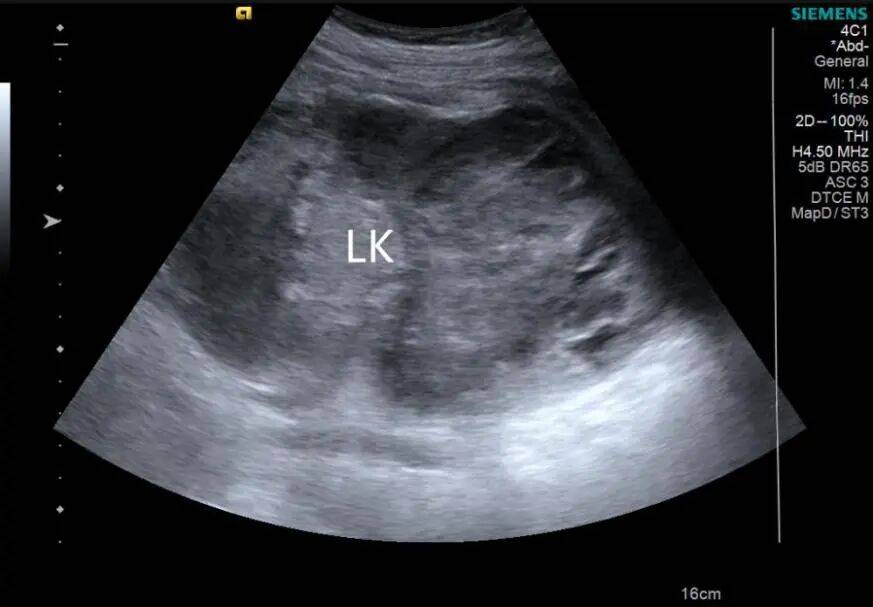

1. 左肾形态失常,体积增大,内部结构紊乱,呈混合性回声,以实性为主,内部可见不规则无回声。CDFI:混合性回声内部及周边未见明显血流信号(图 1、2)。

图 1 灰阶超声示肾癌超声表现( LK 左肾)